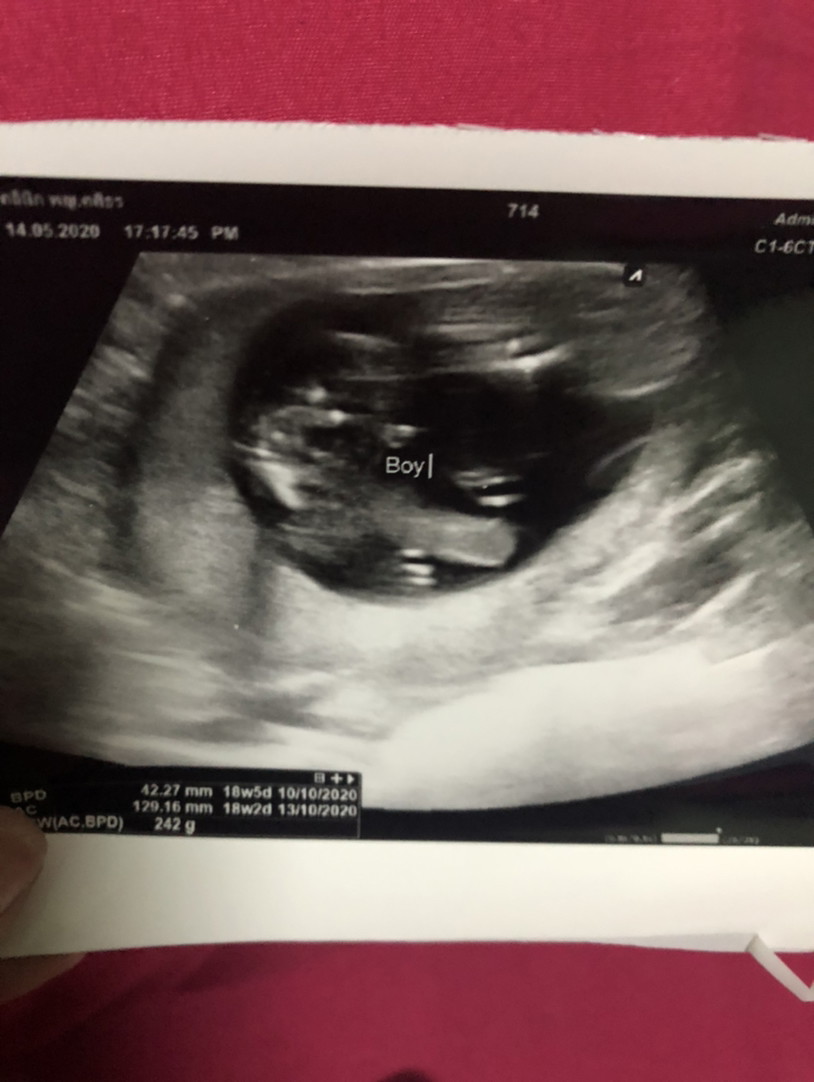

25wชายค่ะ